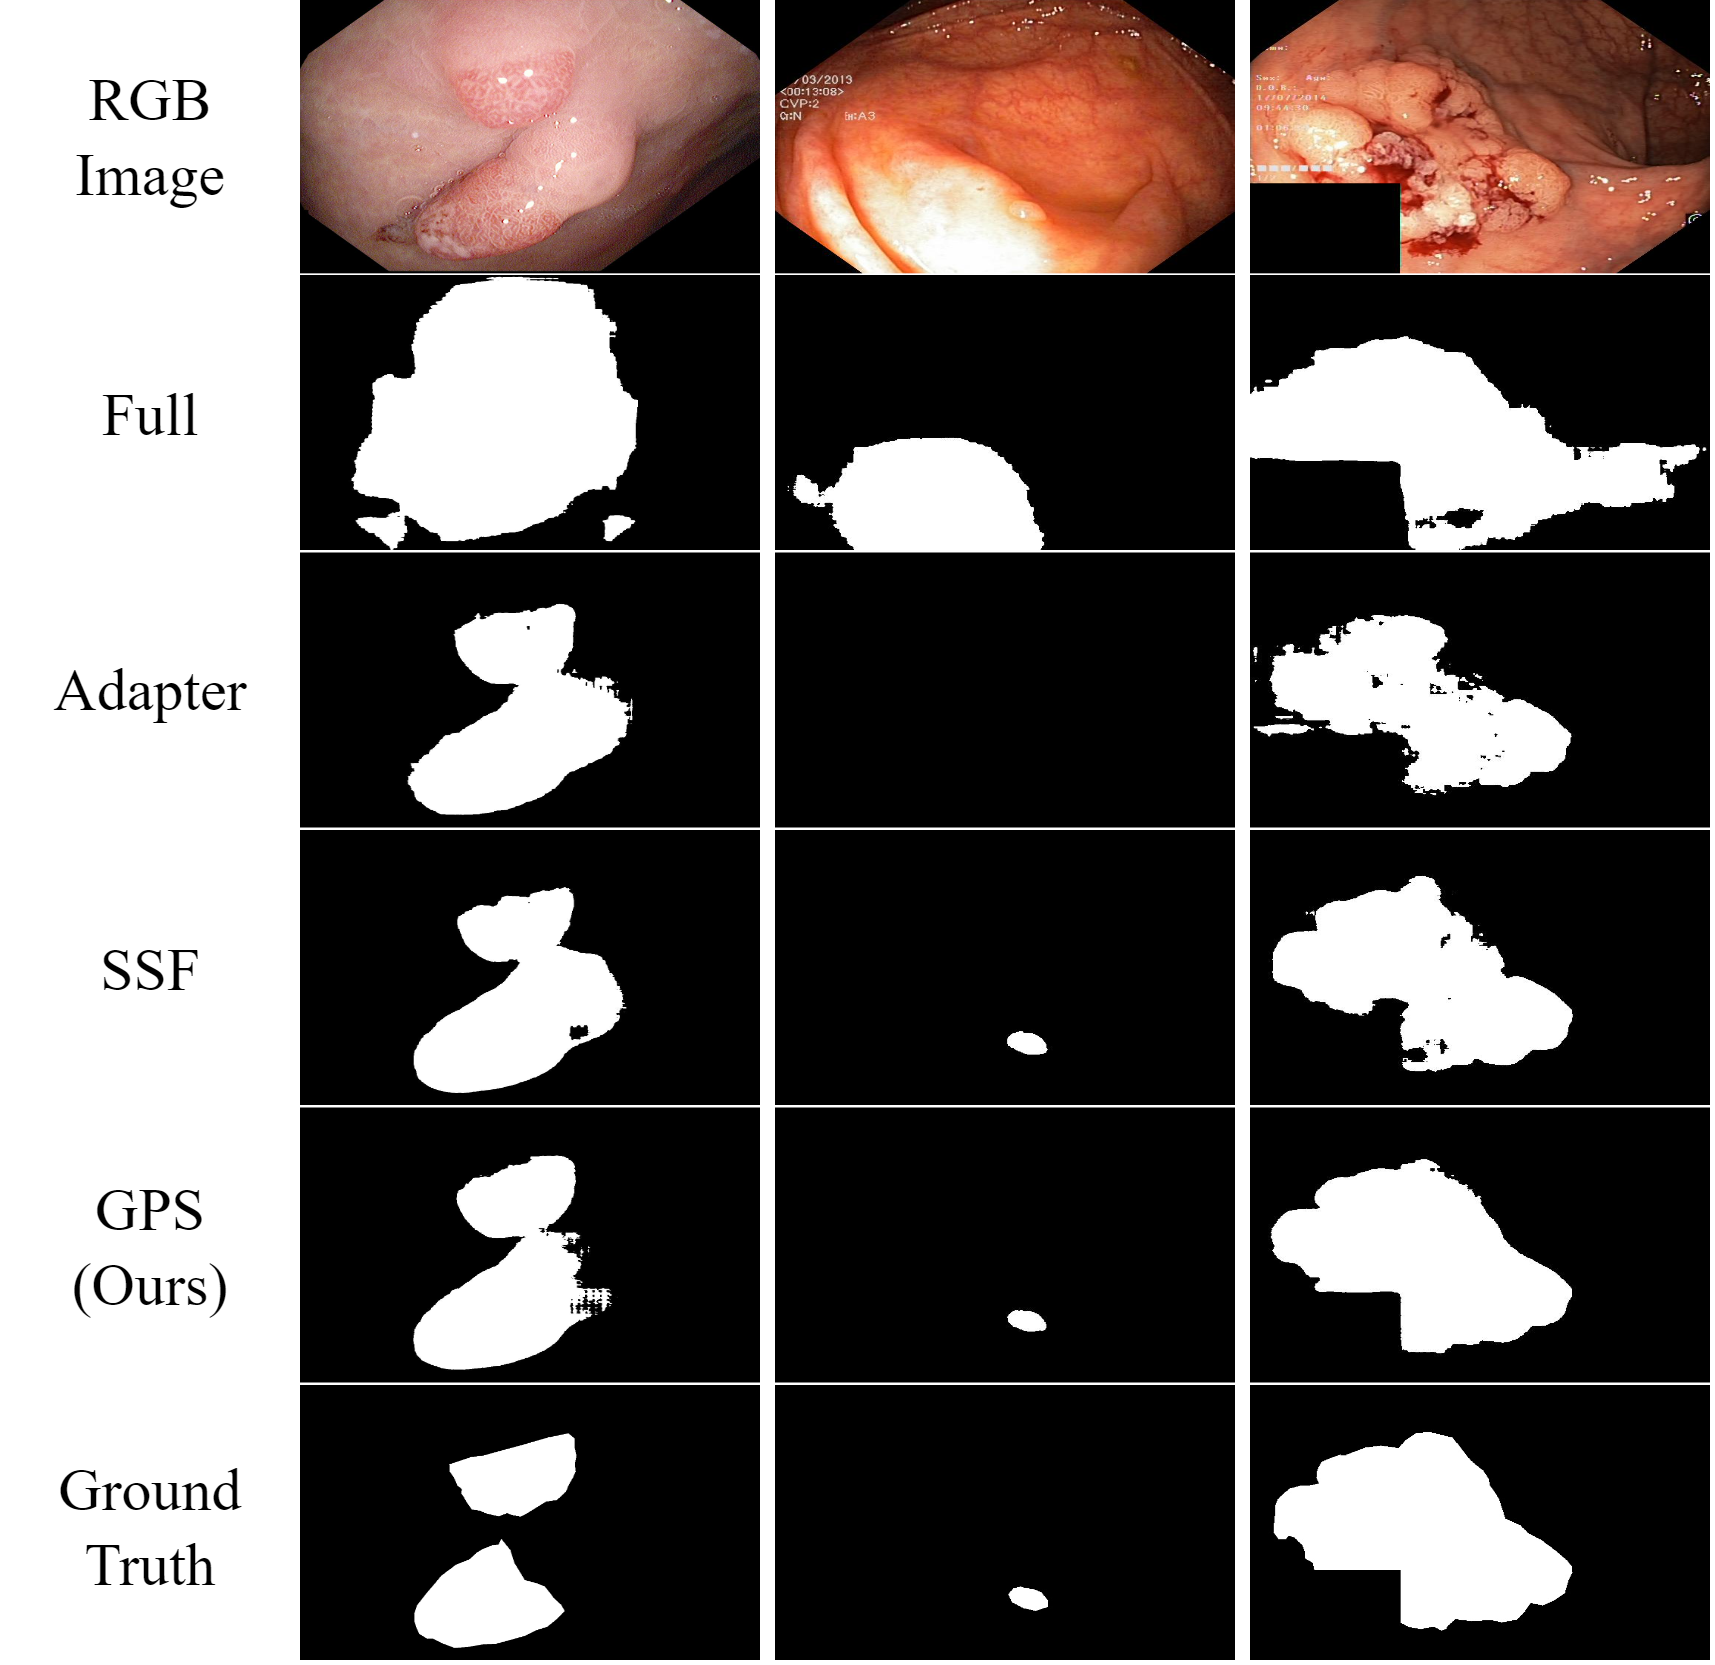

In addition to visual classification tasks, we also explore our method for the task of semantic segmentation. Segment Anything Model (SAM) [48] is a strong foundation model for segmentation. It is pre-trained on a large-scale dataset enabling powerful generalization. However, several studies, e.g. [6], have reported poor performance of SAM on medical segmentation tasks such as polyp segmentation [39]. To address this limitation, they proposed employing Adapter to effectively fine-tune SAM for downstream medical segmentation tasks. Following their experimental setup, we applied our method to SAM and conducted a comparative analysis with other PEFT approaches. Our GPS yielded exceptional results, as shown in Tab. 5 and visually depicted in  Fig. 7 (See Supplementary for more case visualization).

Refer to caption

Figure 7: The Visualization of Polyp segmentation task. Our GPS can still handle difficult segmentation cases compared with others.

Figure 19: The Visualization Result of Polyp Segmentation. Here GT means ground truth. As illustrated in this figure, although SAM and other methods can identify some polyp structures in the image, the result is not accurate. By using GPS, our approach elevates the performance with SAM.

As mentioned in the main body of our paper, our approach demonstrates highly promising results in the field of semantic segmentation. We apply our method on the pre-trained strong segmentation model (SAM) [48] and fine-tune on a medical segmentation task - polyp segmentation [39]. Here, we present more case visualizations, which could directly show the effectiveness of our method, as shown in Fig. 19.